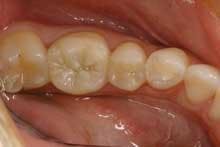

The patient had all the restorations in this quadrant completed, thereby saving the need for multiple appointments and injections. Moreover, and just as important for this patient, her teeth look like teeth again.

Figure 4 shows the final restorations - a high-strength, all-ceramic crown (Lava, 3M) and a conservative Class II direct composite (Premise, Kerr).

From a business standpoint in our office, the fees for an all-ceramic crown, a build-up, and a three-surface Class II composite total $1,618. If they are done at the same time, we will schedule 2.25 hours of total chairtime. This comes out to $719 per hour. If we were to do these restorations separately, our total chair time would be three hours. Our hourly productivity would then be reduced to $539 per hour. From the patient's standpoint, it would require three visits to our office instead of two, as well as having an additional injection.